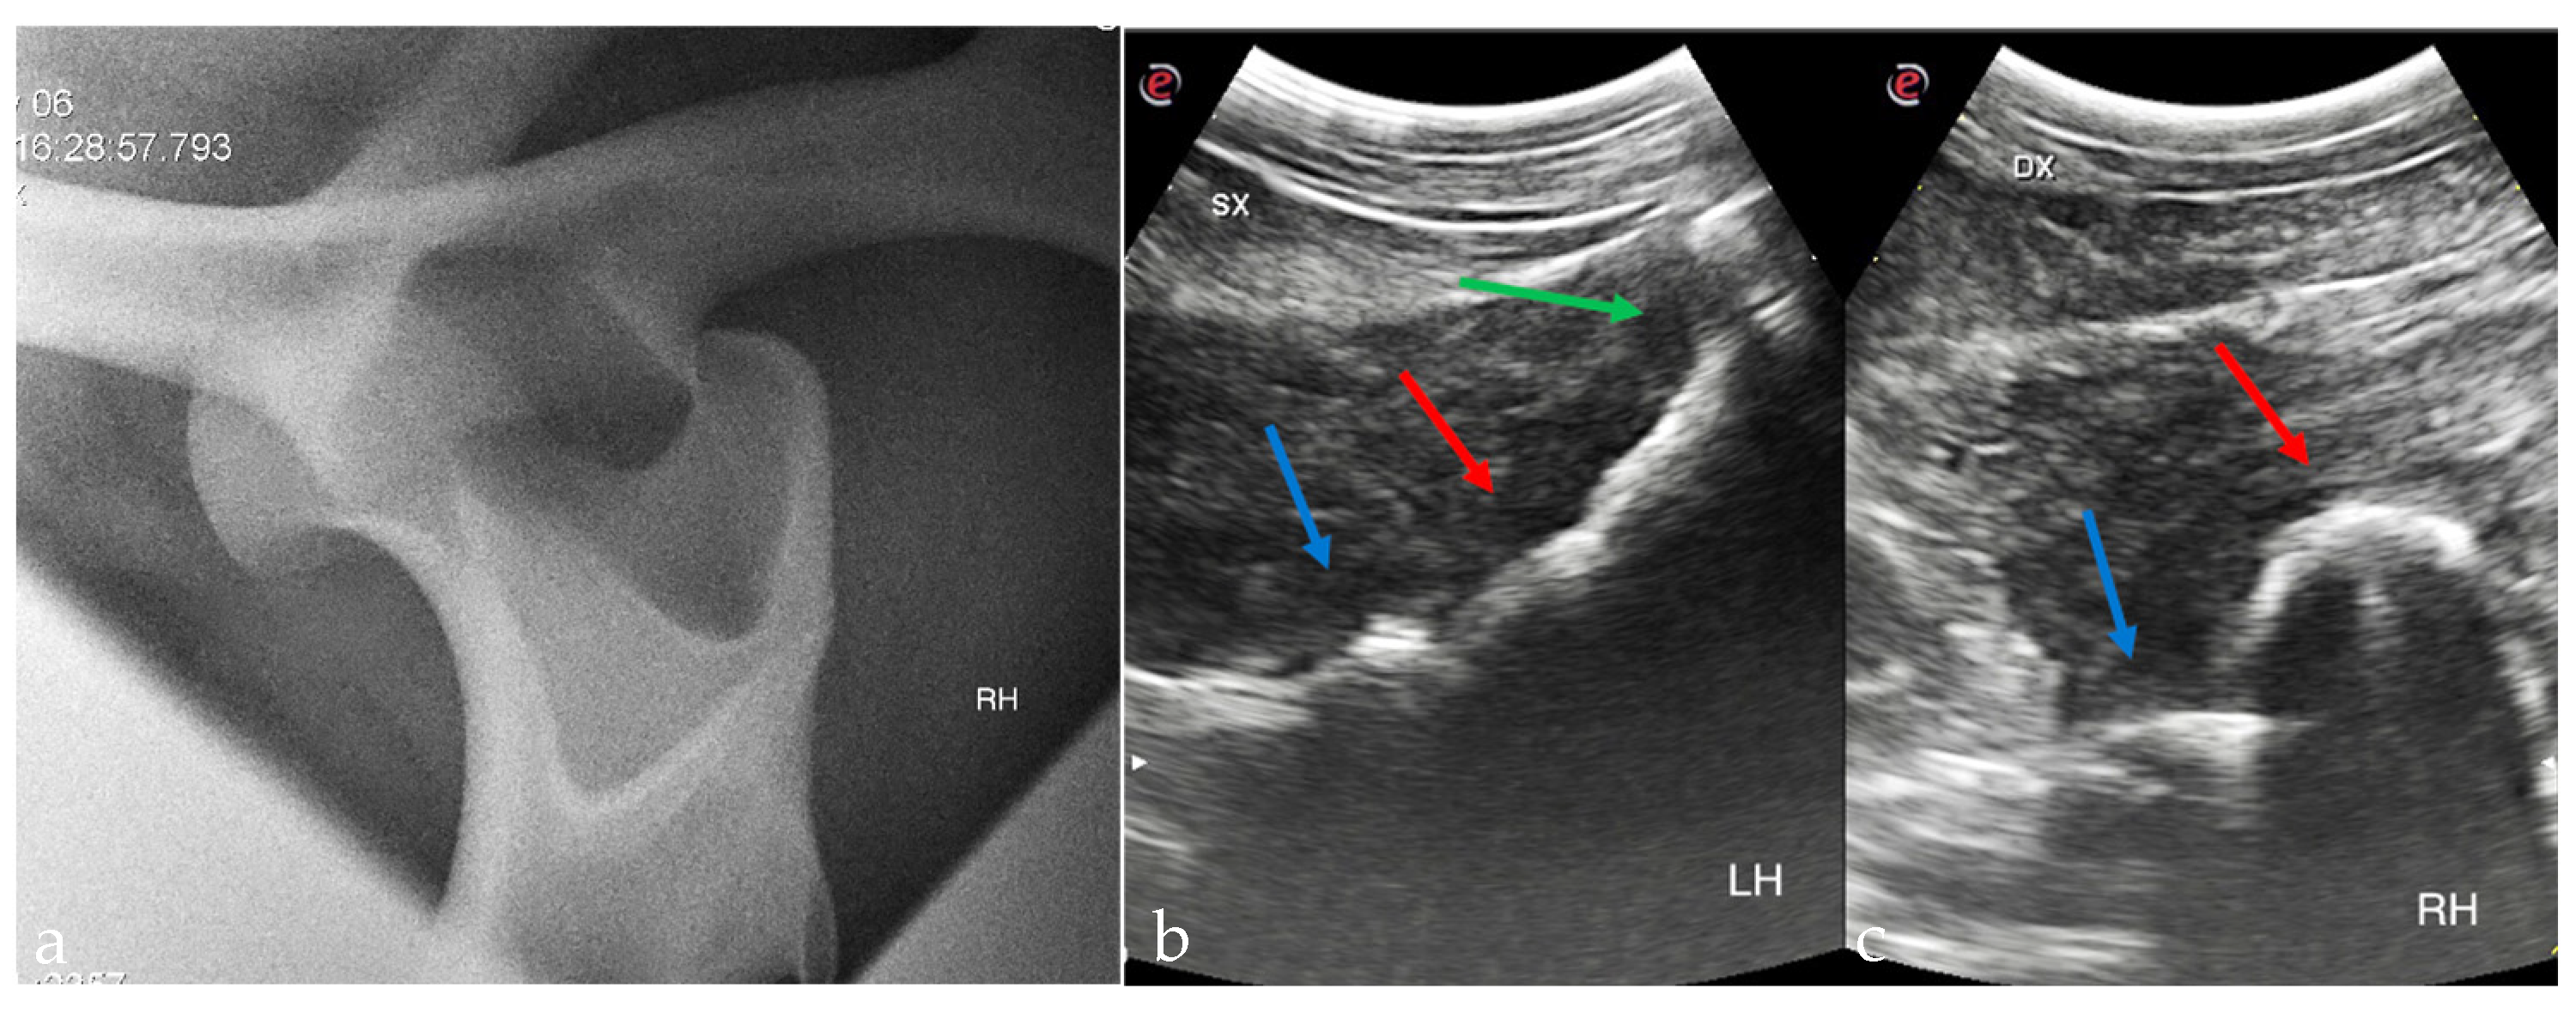

2.2. Diagnostic Imaging